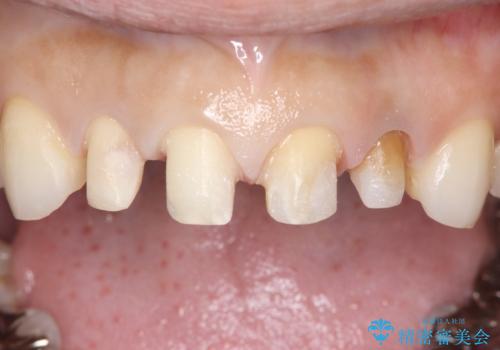

- 上顎の前歯4本が、過去の治療痕による変色や欠けで見た目が気になるとの主訴でご来院されました。患者様は、思い切り笑えるよう自然で美しい前歯を求めていらっしゃいました。そこで、最も天然歯に近い審美性を再現できるオールセラミッククラウンを用いた治療計画を立案しました。歯並びや色のバランスを整え、長期的に安定する美しい口元を獲得することを目指します。

治療はまず、審美性を最大限に高めるために、歯肉のラインや前歯の形を整えることから始めました。その後、4本の歯を丁寧に形成し、金属を一切使用しないオールセラミッククラウンを作製しました。